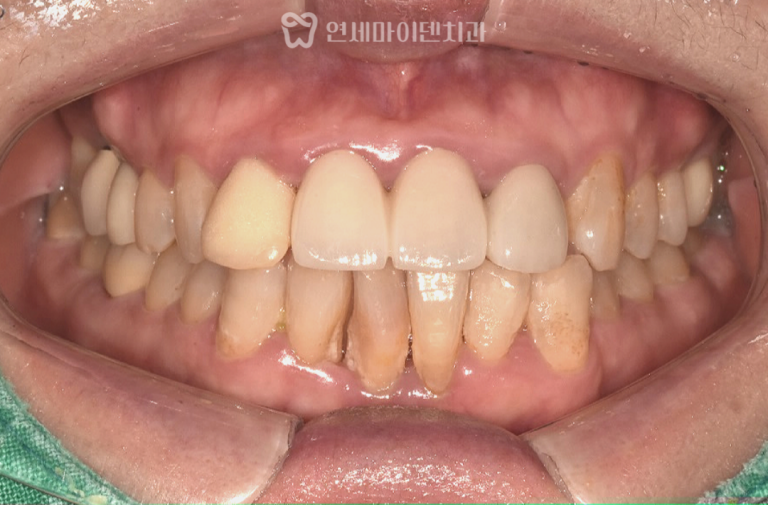

60대 중장년층 치아교정: 치주환자 발치교정 증례 치아교정은 흔히 10대나 20대 청소년,젊은 성인만을 위한 치료라고 생각하기 쉽습니다….